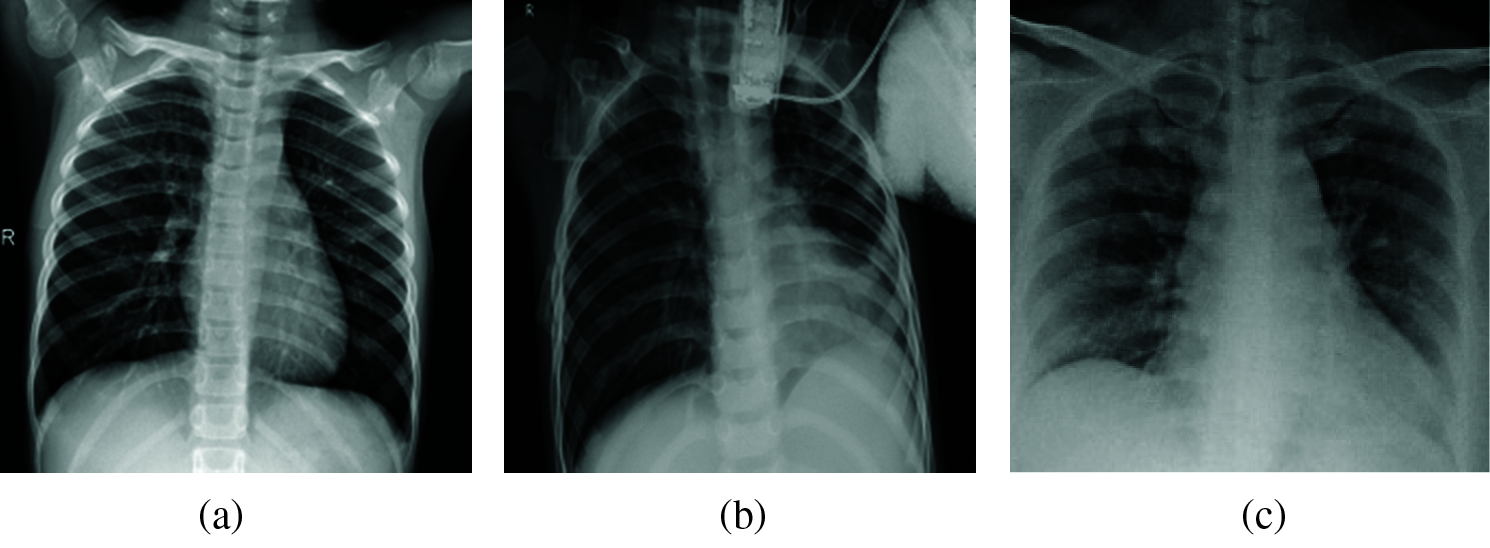

The selected images were then resized to adapt to the input shape of the model. The collected dataset consisted of three different classes: confirmed COVID-19 cases, other pneumonia cases, and normal cases. Fig. 7 shows examples of images from each class.

Figure 7: Example of images from the dataset: (a) normal (b) pneumonia (c) COVID-19

The publicly available sources are described in Tab. 2. Pneumonia and normal X-ray images used in our dataset come from the Kaggle platform2 and comprise 1.341 normal cases and 1.345 other pneumonia cases.